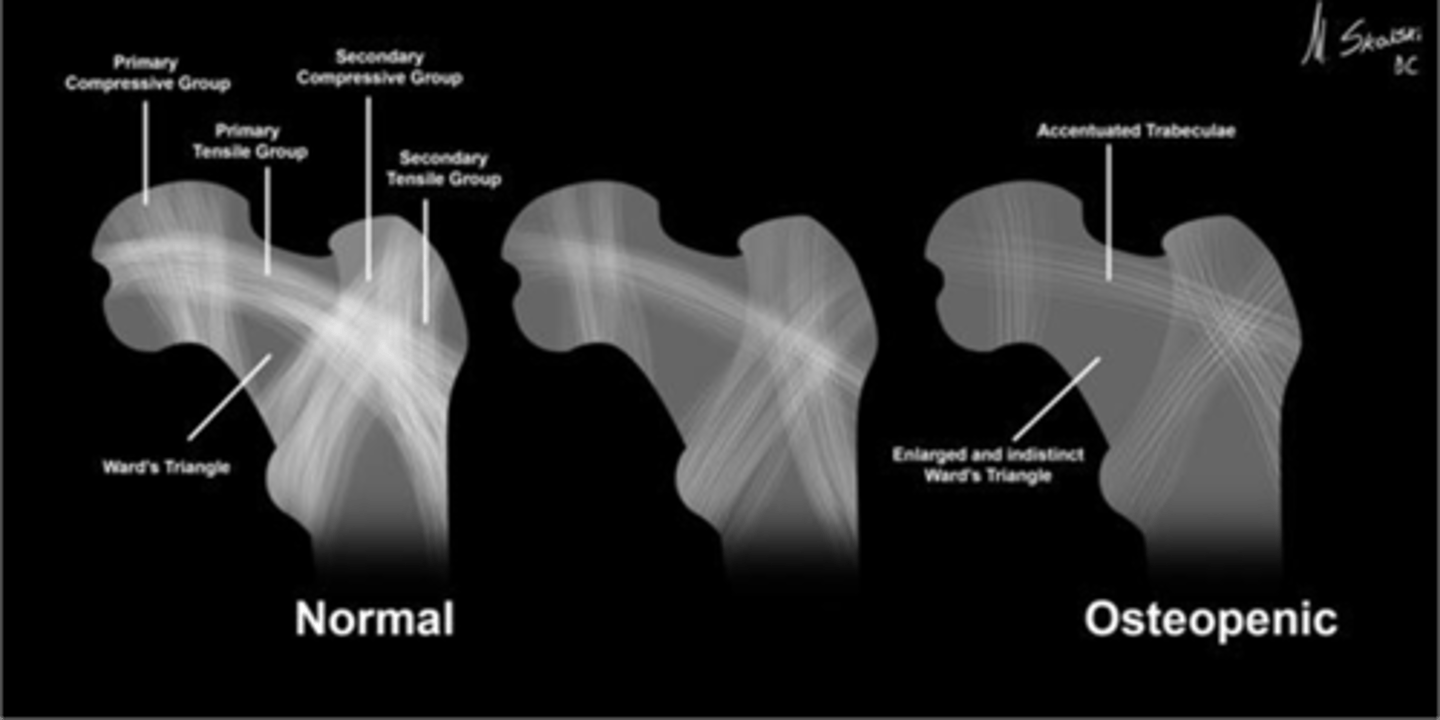

Wards triangle

An area that appears more radiolucent because it is surrounded by an abundance of trabeculae. The 1˚ and 2˚ compressive and tensile groups of the proximal femur leave a small region to appear more lucent

<p>An area that appears more radiolucent because it is surrounded by an abundance of trabeculae. The 1˚ and 2˚ compressive and tensile groups of the proximal femur leave a small region to appear more lucent</p>

New cards

Osteopenia

Wards triangle becomes enlarged as bone density reduces, signifying _____

<p>Wards triangle becomes enlarged as bone density reduces, signifying _____</p>